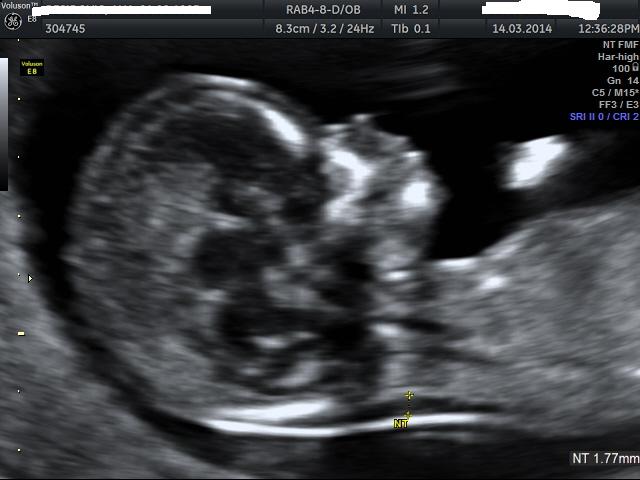

12weeks + 6 days

Wow definitely boy....perfect boy nub there!! Congrats x